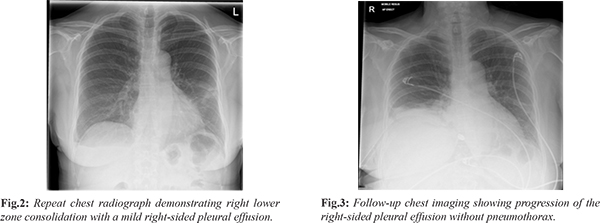

Three days later, she presented again to the Emergency Department with increasing right-sided chest pain. Clinical examination remained unremarkable. However, repeat chest radiography revealed right lower zone consolidation with a mild pleural effusion [Fig.2]. Her prior history of trauma was not adequately considered, and she was referred to the Same Day Emergency Care (SDEC) unit. A provisional diagnosis of lower respiratory tract infection was made, and she was managed with oral antibiotics and analgesics, with advice for follow-up imaging. Subsequently, the patient reported with new-onset dyspnea and persistent right-sided chest pain. On examination, reduced air entry was noted on the right side. Repeat chest imaging demonstrated a progressive increase in the right-sided pleural effusion without evidence of pneumothorax [Fig.3]. A subsequent computed tomography (CT) scan of the chest identified multiple right-sided rib fractures along with a moderate pleural effusion, suggestive of an evolving haemothorax [Fig.4,5].

The patient was transferred to the resuscitation area, where an intercostal chest tube was inserted [Fig.6], yielding approximately 1000 mL of blood. Following cardiothoracic consultation, she was admitted under the surgical team for further management. Her clinical condition improved progressively [Fig.7,8], and the chest tube was removed after seven days. She was discharged in stable condition with planned follow-up in the surgical outpatient clinic.